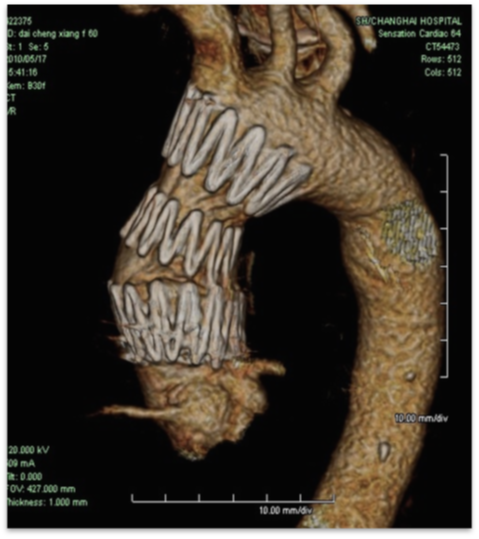

【专用器具研发】ARISE临床试验进展

在国际上,多项临床试验正在积极推进。Gore公司资助的ARISE系列研究(ARISE I、II、III)进展顺利。其中,ARISE研究评估GORE® Ascending Stent Graft在DeBakey I/II型主动脉夹层治疗中的应用。

这款专用支架的特点包括:

更大口径:34mm-53mm

三个长度尺寸:7cm、8cm、10cm

精确释放设计:分步释放,成角控制

避免冠脉覆盖:sleeve pullback机制、近端小裸段设计。

ARISE I已完成43例入组,ARISE II于2023年12月完成招募,入组标准已从慢性夹层扩展至急性夹层。